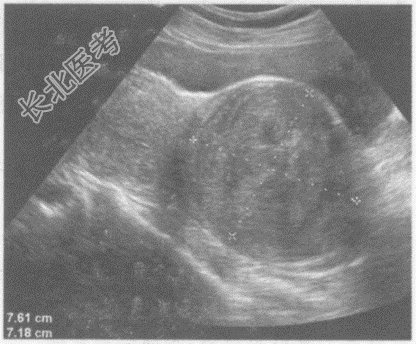

- 单项选择题临床资料:女性患者, 42岁,自述下腹坠胀, 月经量增多3年余。

超声综合描述:子宫前位, 宫颈部可见7.8cm×7.2cm低回声区,边界清晰, 形态规则,内回声不均匀, 呈漩涡状,向外突起, CDFI:周边可见少许血管绕行, 呈动脉血流频谱。见下图及彩图105。

超声提示: A、阔韧带肌瘤

B、子宫颈肌瘤

C、子宫颈妊娠

D、子宫颈癌

E、子宫腺肌病